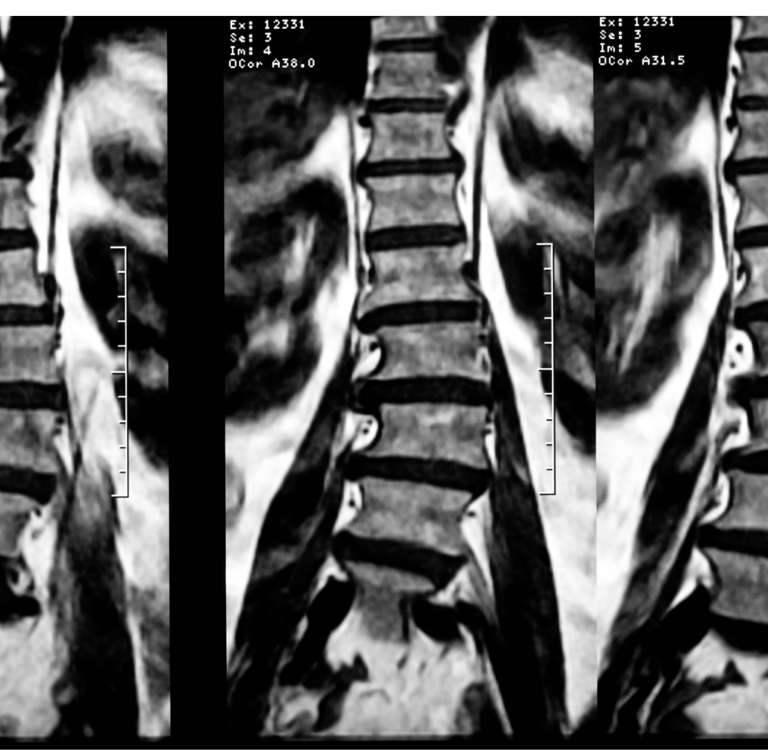

FISIOTERAPIA ESPECIALIZADA EM ESCOLIOSE

A Fisioterapia para escoliose é um tratamento personalizado, baseado em exercícios específicos com comprovação científica. Seguimos as diretrizes da Sociedade Internacional de Tratamento da Escoliose (SOSORT) e, através de uma avaliação individual, traçamos um plano de tratamento visando o equilíbrio e a estabilidade do corpo. Utilizamos técnicas modernas e atuais, com o objetivo de não apenas tratar a condição, mas também melhorar a qualidade de vida do paciente, permitindo maior facilidade nos movimentos e uma postura mais correta. Entre os principais métodos utilizados destacam-se: